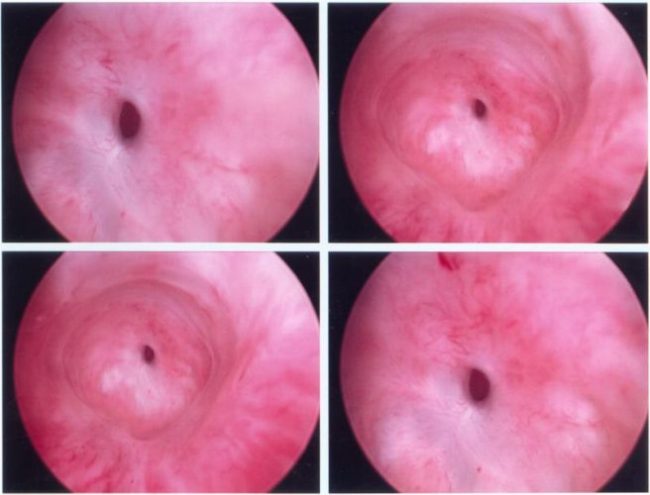

Notice: Trying to access array offset on value of type null in /home/u9176434/en.uretradarligi.com/wp-content/plugins/js_composer/include/autoload/vc-shortcode-autoloader.php on line 64 Notice: Trying to access array offset on value of type null in /home/u9176434/en.uretradarligi.com/wp-content/plugins/js_composer/include/autoload/vc-shortcode-autoloader.php on line 64 The Treatment of Urethral Stricture The treatment of urethral stricture does not involve medications. It involves three surgical methods, which include dilation, endoscopic…